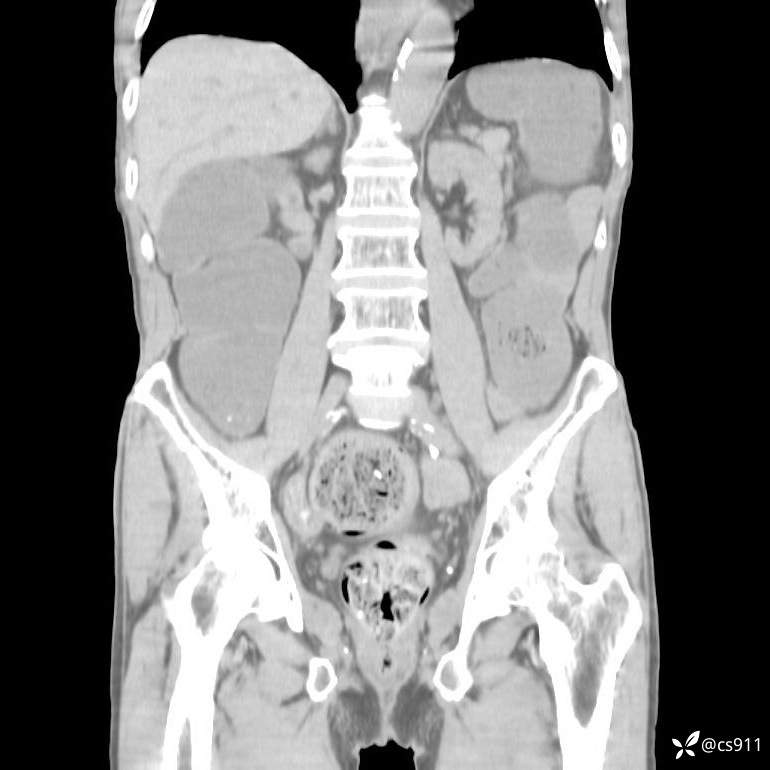

急腹症之急诊CT,原因?答案公布

男,77岁,腹痛、腹胀伴恶心呕吐1天。呕吐胃内容物,非喷射性呕吐,有咖啡色样胃内容物,诉有胃穿孔病史。查体:全腹平,下腹部压痛,全腹无反跳痛,叩诊呈浊音,移动性浊音阴性,肠鸣音减弱,1-2次/分。肛检:直肠未扪及明显肿物,可触及大量粪块。

T 36.6℃ P 80次/分 R 26次/分 BP 100/60mmHg

白细胞(WBC) H 14.55 10e9/L 4-10

中性粒细胞百分率(NEUT%) H 85.7 % 40-75

血淀粉酶(AMY) HH 1859 U/L 35-135

癌胚抗原(CEA) H 27.44 ng/ml 0-5

呕吐物 潜血试验 * 阳性 阴性

患者轮椅入室检查神志清楚, 能配合摆位和呼吸